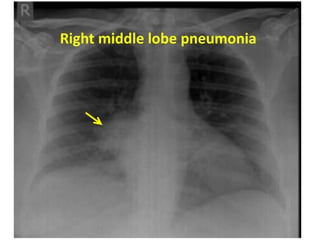

E.g. : Right middle lobe consolidation blurs the heart

border

Right middle lobe infiltrates (or early consildation)

Right middle lobe consolidation

Figure 7: Right middle lobe pneumonia

Right middle lobe pneumonia